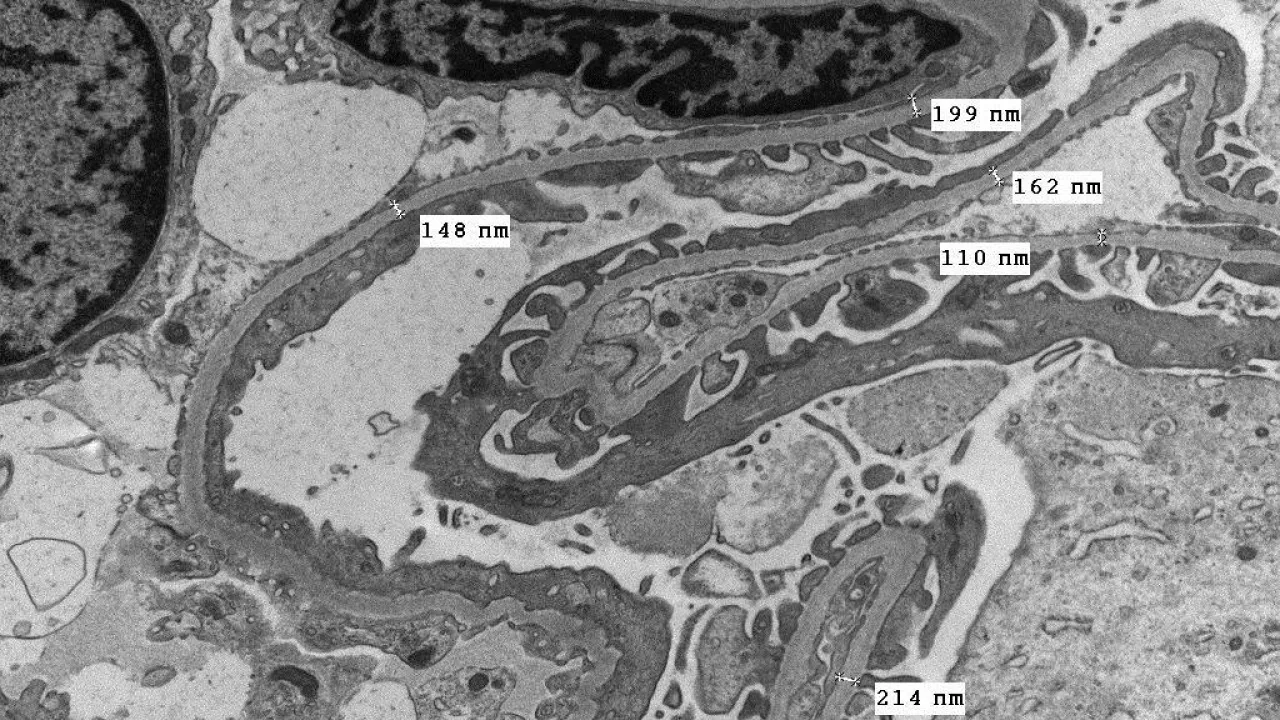

Kidney, Glomerular basement membrane with structural abnormalities